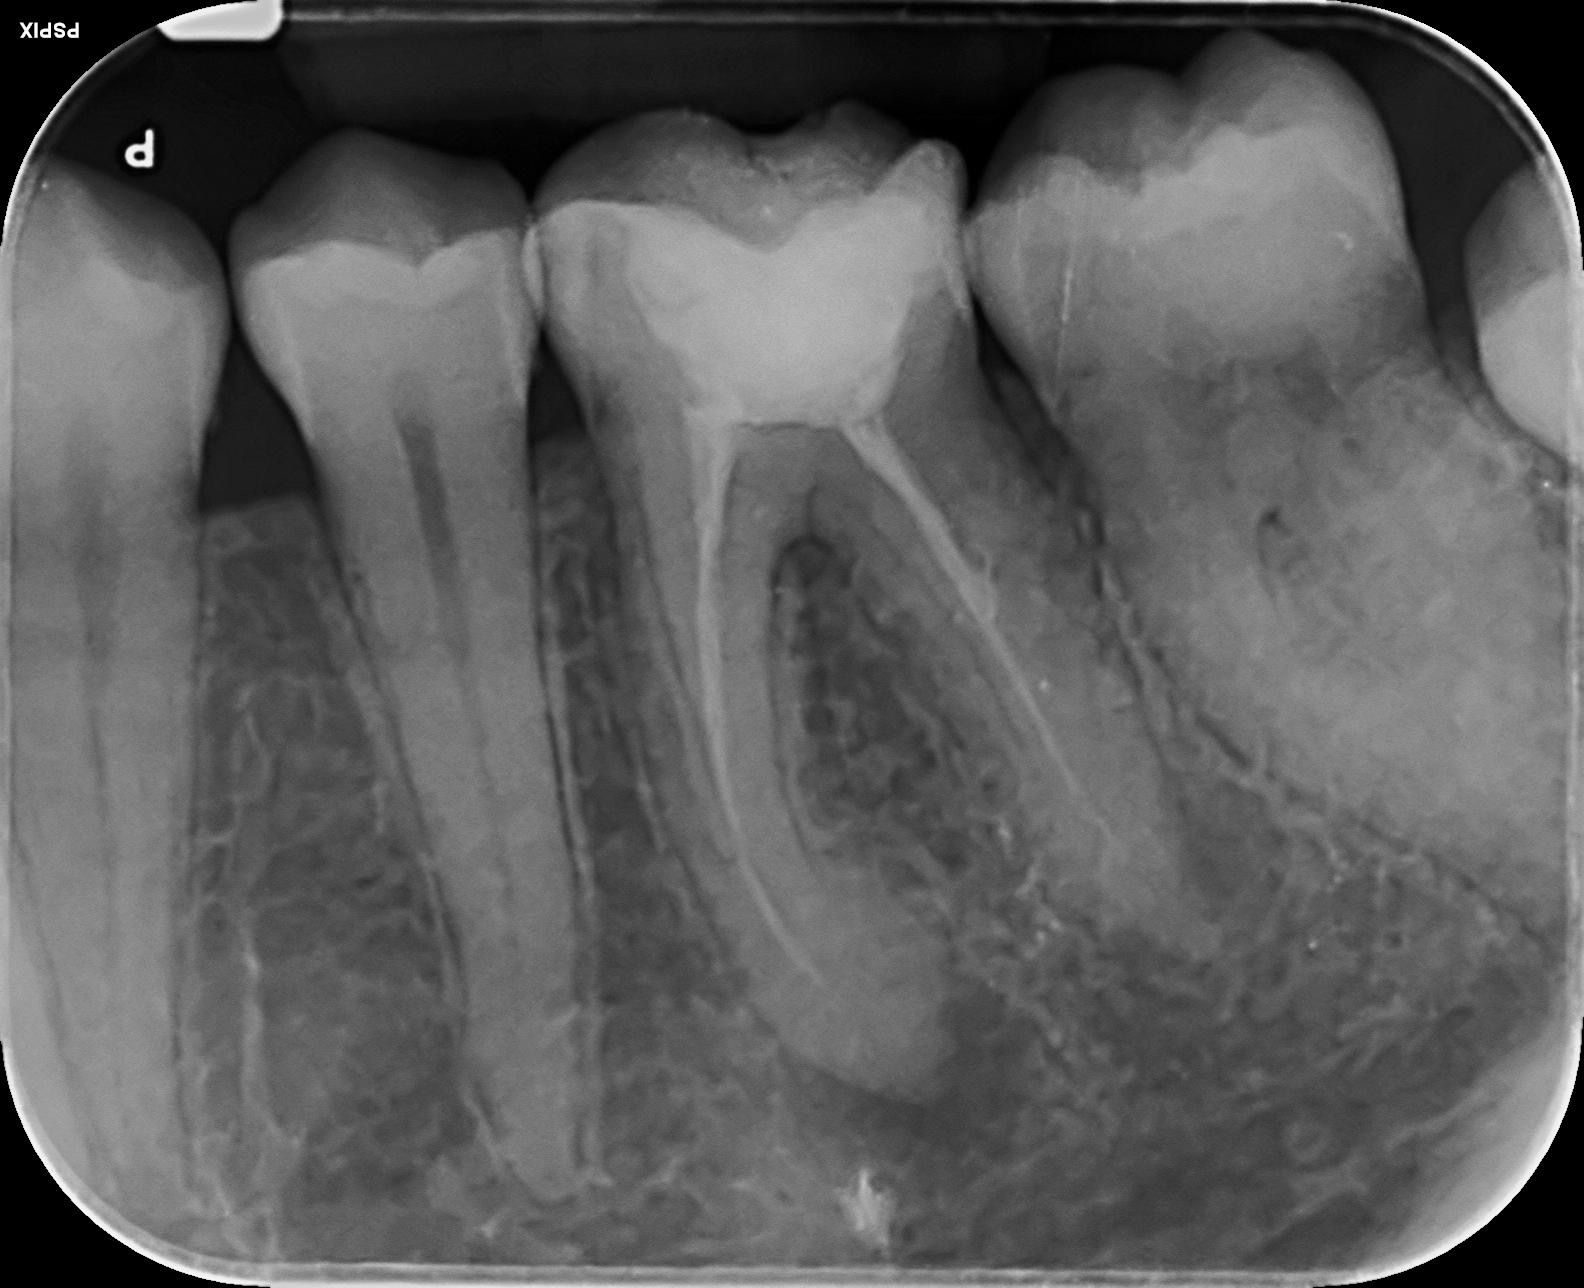

Casos clínicos realizados por la Dra. María Medina

Antes

Déspues

Caso 2